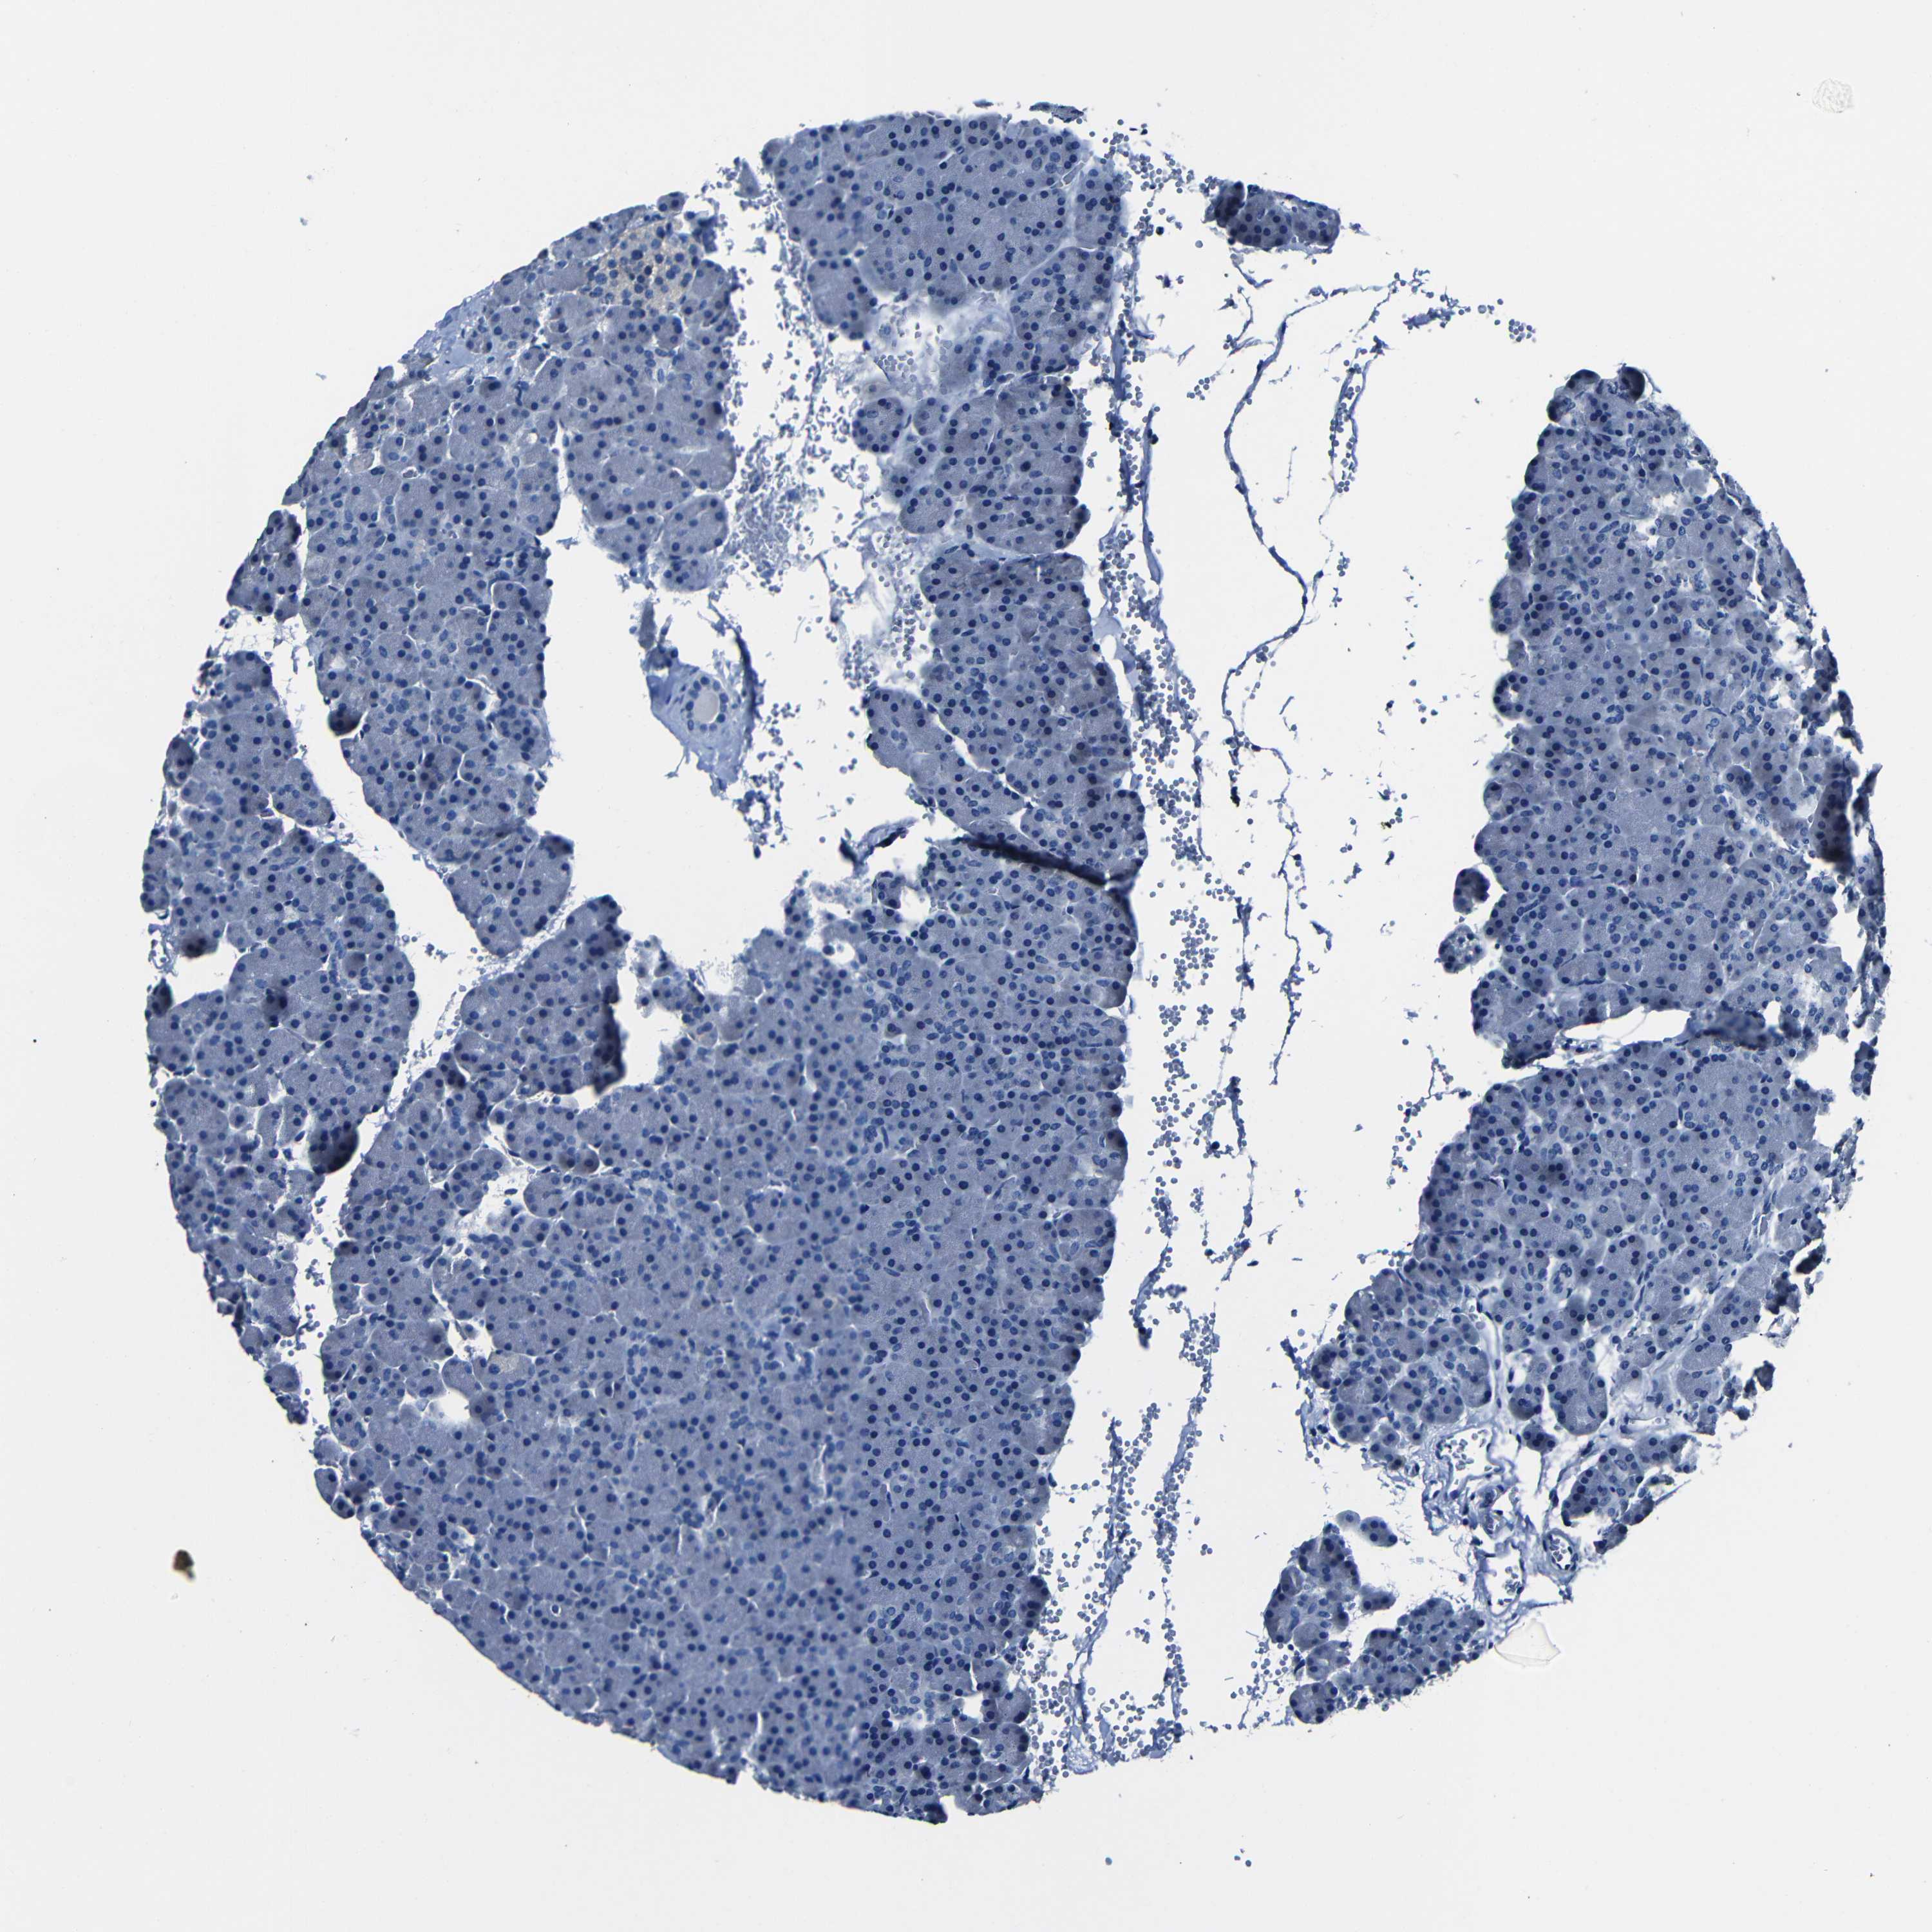

PANCREAS - Antibody stainingi

Antibody staining in the annotated cell types in the current human tissue is reported as not detected, low, medium, or high, based on conventional immunohistochemistry profiling in selected tissues. This score is based on the combination of the staining intensity and fraction of stained cells.

Each image is clickable and will lead to virtual microscopy that enables deeper exploration of all samples and also displays staining intensity scores, fraction scores and subcellular localization as well as patient and tissue information for each sample.

Antibody HPA013656

Exocrine glandular cells Not detected

Pancreatic endocrine cells Not detected